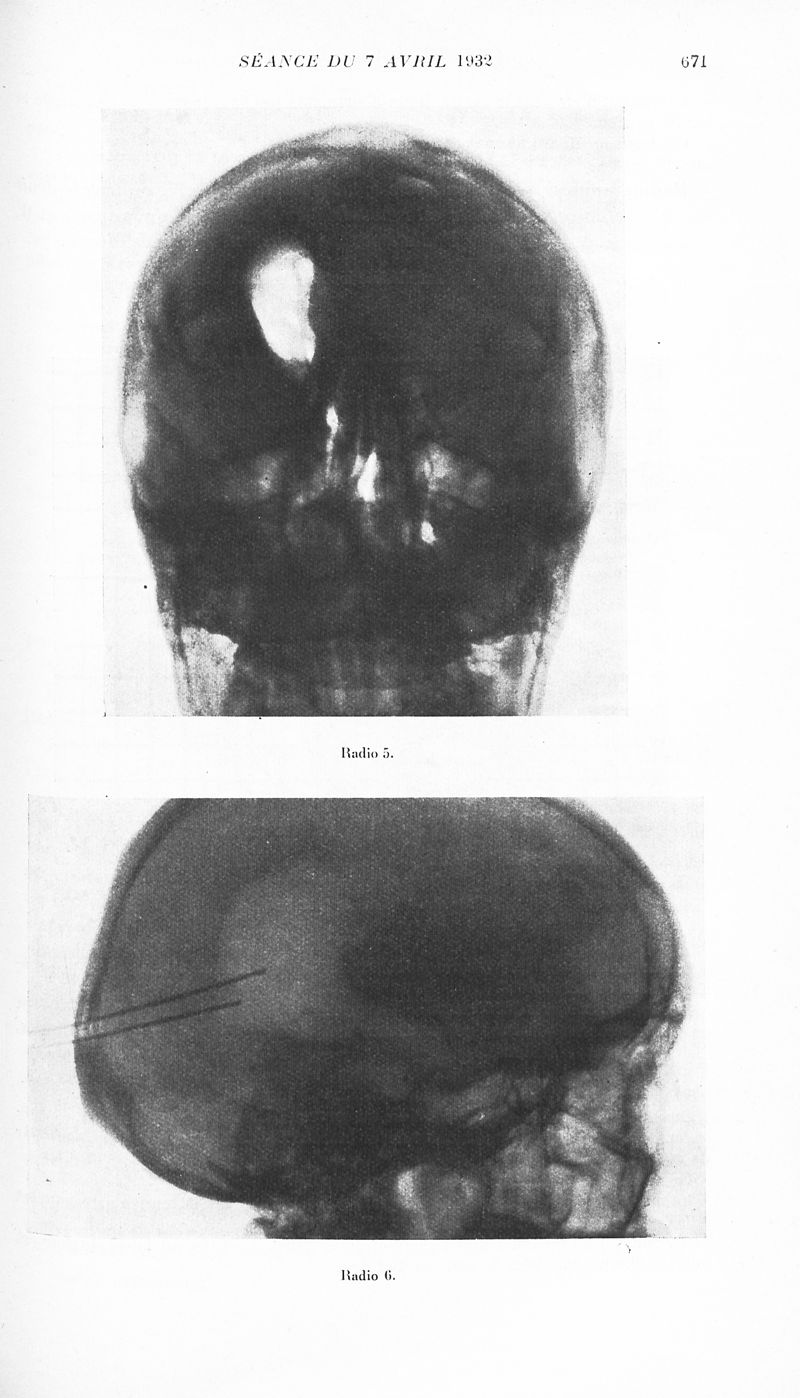

Revue neurologique

1932, vol 1. - Paris : Masson , 1932.